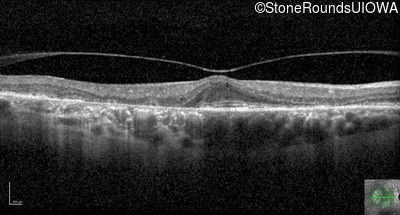

Optical Coherence Tomography - Left - 20/25 -1

Exemplar / OCT Stack